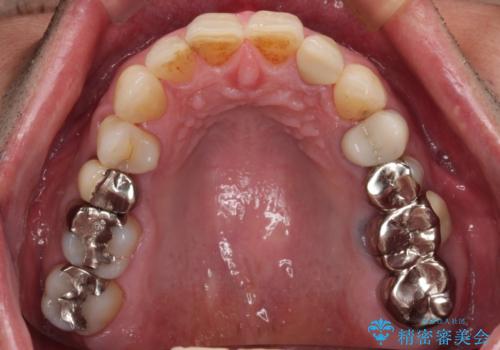

- 前歯の根管治療の際に、一時的に見た目を回復したままの状態で放置してしまったとのことで来院された患者様です。

土台の状態は良好であったため、仮歯に置き換えた上でオールセラミッククラウンにて補綴治療を行うこととしました。